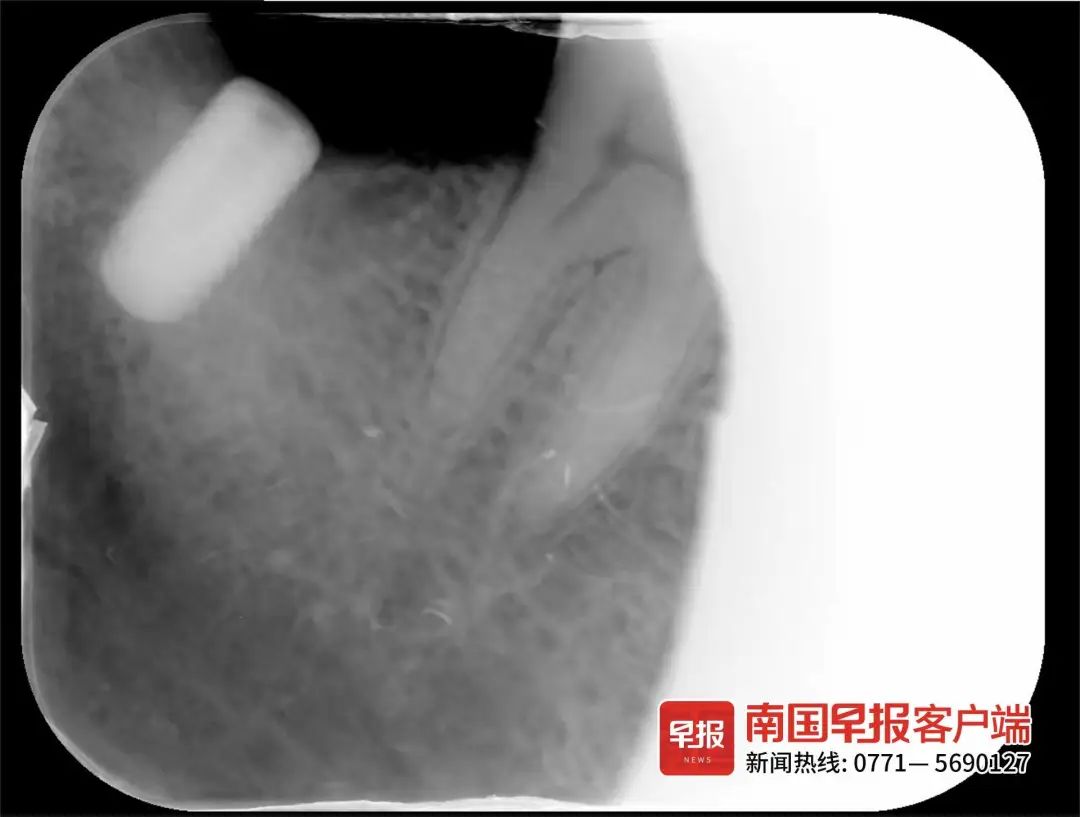

潘先生此前种植的牙齿牙冠断裂,只剩螺丝(图中白色部分)残留在牙床中。受访者供图

由于双方无法达成一致,螺丝至今仍残留在牙床内。